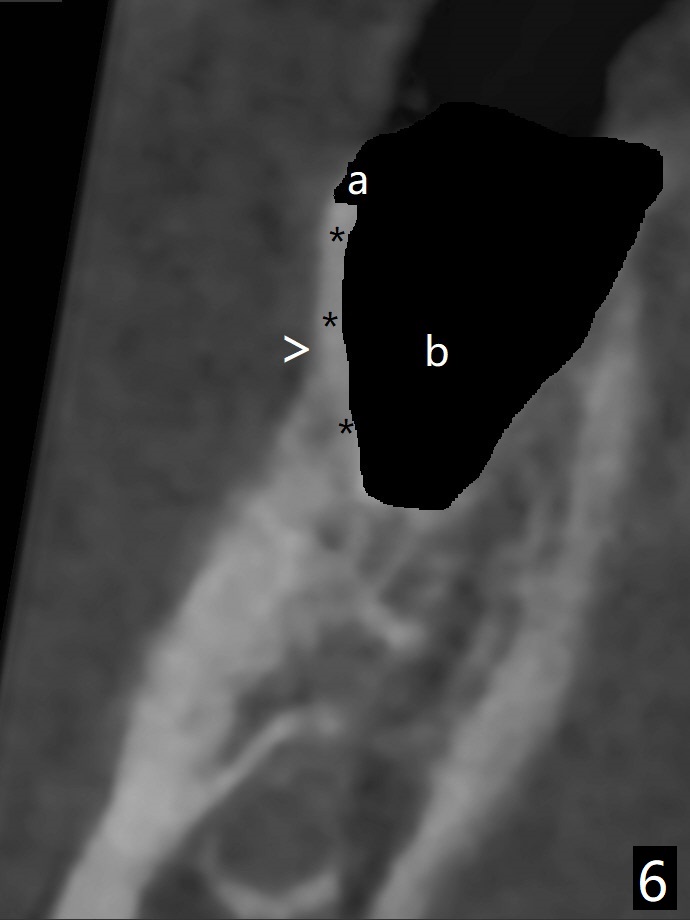

The tooth #30 of a 47-year-old woman has lower buccal crest (Fig.1-3 ^). To prevent post-extraction buccal plate collapse, closed socket shield (Fig.6,8-10 *) will be conducted in the mesial (Fig.1,4-6) and distal (Fig.2,7-10) roots. To decrease vibration, the buccal edge of the roots will be trimmed first (Fig.5,6 a) before root section (Fig.6 b).